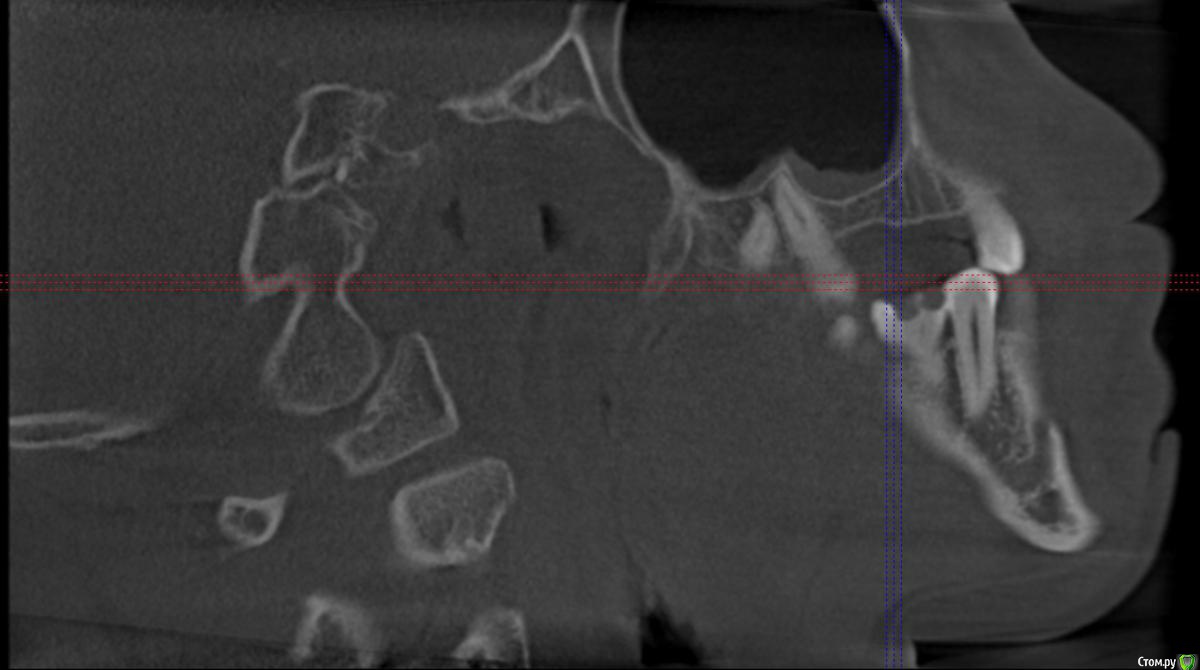

Секатор Опубликовано 4 октября, 2015 Поделиться Опубликовано 4 октября, 2015 (изменено) Здраствуйте,уже писал,но проблем много,но сча есть снимки зд(ссори за флуд).Начну издалека года два летом примерно неделю начили болеть зубы справа с отдованием в ухо и висок,оперативно ничего не делал(спас ал алкоголь),но я решил,что это 8-ки,и за зиму последнию все удалил,но отдования в висок и болезненность уха осталось,много времени прошло после удаления.Напряжение у виска и в области уха,взгляните на мою 6 справа,дно пазухи деформировано под её давлением,боли в области зуба нет-она причина?По лор все чисто,как будто болит зуб отдовая в ухо и висок,но без боли в области челюсти.Ближе к внутренней стенки пазухи и заходя на неё сформирован остроконечный конус дном пазухи,вследствии давлении корня зуба. Изменено 4 октября, 2015 пользователем Секатор 1 Ссылка на комментарий

Секатор Опубликовано 15 октября, 2015 Автор Поделиться Опубликовано 15 октября, 2015 Здравствуйте,сос...Рано поспешил радоваться,дело в следующем мне хорошо обкололи,и сверлили 47,положили мышьяк,ухо прошло на два часа,как в сказке был,но боль снова началась.Невралгия нерва по-любому есть,а вот причина!И,что где-то рядом с зубами.Все-таки планирую удалять 7 справа сверху,а ккак быть?Придётся методом тыка,у 7 корня небольшое утолщение слизистой пазухи,но вот ещё что,на уровне 5,6 была киста пазухи,прошла после удаления зубов. Ссылка на комментарий

Секатор Опубликовано 15 октября, 2015 Автор Поделиться Опубликовано 15 октября, 2015 (изменено) И,ещё раз прошу взглянуть смотрите,как деформирована внутреннеяя стенка пазухи зубом,у дна.Может корень подцепил,стенку пазухи? Изменено 15 октября, 2015 пользователем Секатор Ссылка на комментарий